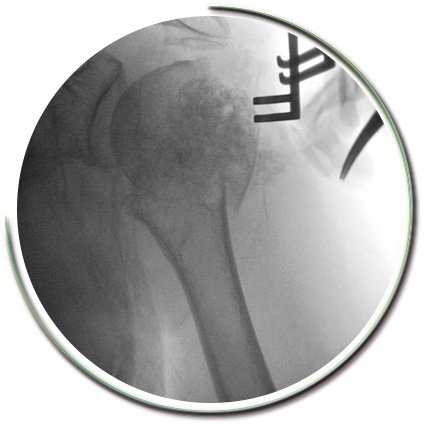

Parçalı kırıklarda kaynama sorunları ve işlev kaybı oluşmaması amacıyla sınırlı girişimsel cerrahi müdahale gerekebilmektedir. Kırık parçaları için çok kıymetli olan kanlanma bozulmadan (travmanın kendisi kanlanmayı yeterince etkileyebilir) kırık tespiti güçlü bir şekilde yapılabilmektedir. Kırık düzeltilmesi, açılan kas pencerelerinden yapılır. Parçaların tamamına hakim olabilmek amacıyla dikişler ve kilitli vidalı plaklar kullanılır. Kullanılan pencereler yerleştirilen plaklara göre oldukça küçük boyutlardadır. Pencerelerin bölgeden geçen sinirlere uygun mesafede olması gerekir.

Tespit gücü yüksek implantlar sayesinde birkaç hafta içerisinde, hastalar günlük hareketlerini sağlayabilecek ve kişisel ihtiyaçlarını giderebilecek hale gelebilmektedir. Böylece erken rehabilitasyon ve normal hayata hızlı bir dönüş sağlanabilmektedir..